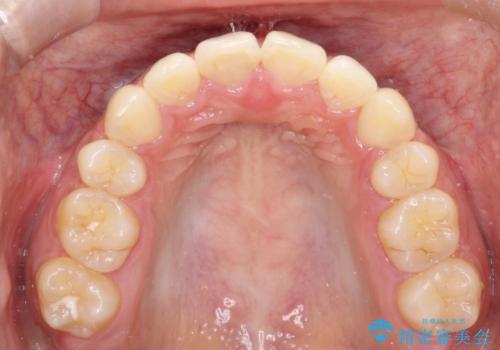

- 前歯の凸凹を主訴に来院されました。

予想治療期間2年でしたが、実際は1年半ほどで終了し満足していただきました。

小臼歯抜歯(上顎4番)して矯正治療を行なったことで、口元もスッキリしました。